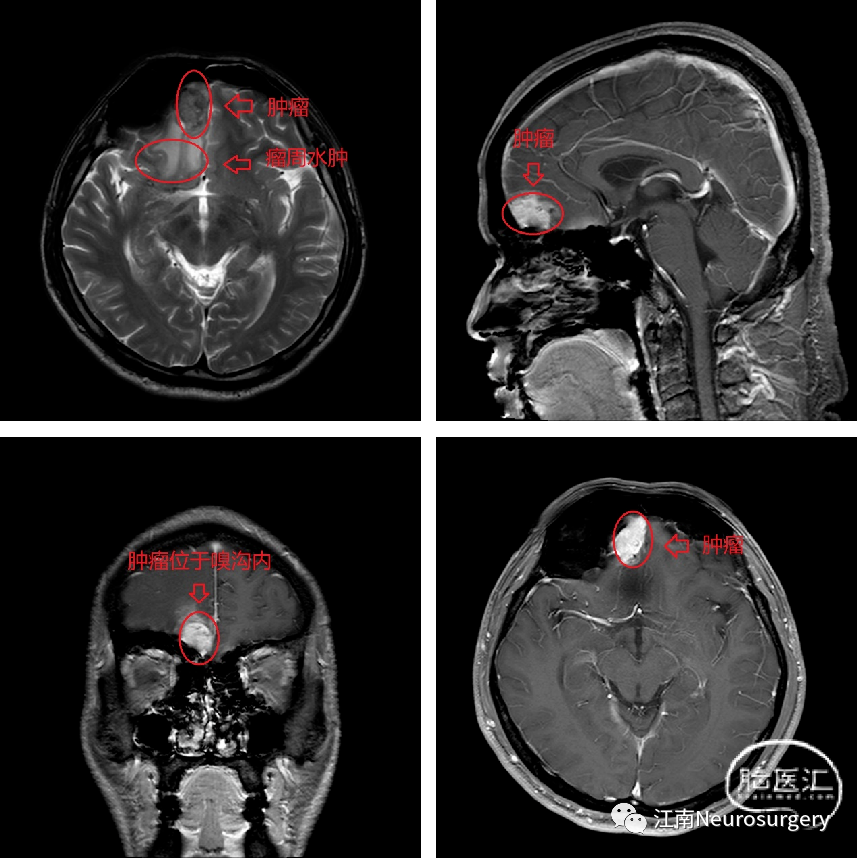

入院后完善检查,查颅脑平扫+颅脑增强+头MRA(TOF)+头CE-MRA(3.0T)提示(图1):右侧额叶占位伴水肿,邻近白质纤维束受压中断,考虑:不典型脑膜瘤。患者颅内占位诊断明确,周围占位压迫所致水肿效应明显,于2022-10-24日全麻下行“额下入路脑病损切除术”。患者气管插管全身麻醉后,仰卧位,头抬高,常规消毒铺巾单。切开皮肤,皮下组织,帽状腱膜,游离皮瓣。剥离骨膜。钻孔,铣刀切开骨瓣,悬吊硬膜,见右侧额窦开放,予碘伏交替双氧水冲洗两次,去除额窦黏膜,予骨蜡封闭窦腔,四周悬吊硬膜止血,人字型剪开硬膜,见额部皮层张力较高,予右侧经外侧裂打开蛛网膜下腔释放脑脊液,见额叶明显塌陷,上抬额叶,中线旁右侧嗅沟区见质韧灰白色肿块,肿瘤大小约4*3.5*4.5cm,分离肿瘤和周围脑组织的界面,保护好周围的动脉和静脉。电凝肿瘤表面,使肿瘤缩小(图2A);沿肿瘤与正常脑组织界面分离(图2B);分块切除肿瘤,使肿瘤体积缩小(图2C);进一步释放脑脊液,使脑组织塌陷,创造更大的手术空间(图2D);在分离的肿瘤-脑组织界面填入明胶分隔(图2E);电凝肿瘤表面使其进一步缩小(图2F);铲除肿瘤基底(图2G);肿瘤切除后所剩残腔,无出血(图2H)。瘤腔充分止血后,止血纱覆盖瘤腔,流体明胶填塞,采用部分肌肉筋膜代替硬膜,水密缝合硬膜,骨瓣回纳,采用bioplate连接片3套固定。皮下仔细止血,逐层缝合肌肉及帽状腱膜,予倒刺线皮内缝合头皮。术后复查MRI见肿瘤切除满意,未见明显残留(图3)。术后病理结果提示:右侧额叶脑膜瘤,肿瘤组织呈侵袭性生长,部分区域细胞丰富,有异型,核分裂像可见(图4)。患者手术恢复良好,顺利出院。

图1. 头颅MRI示嗅沟肿瘤强化。